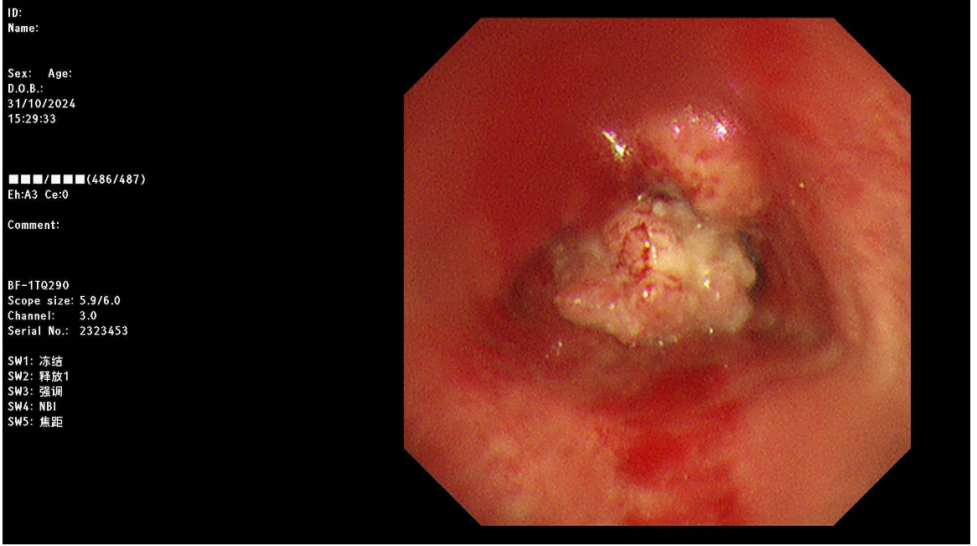

患者杨某,男,82岁,四川省成都市人,出现胸闷、气短2周。2024-10-21患者突发胸闷、气短加重,伴痰中带血,CT检查提示气管隆突区见软组织结节影,形态欠规则,较大截面约2.6cmx2.7cm,邻近气管壁稍增厚,局部管腔变窄。华西医院行支气管镜检查:气管下段隆突处菜花样新生物阻塞致气管下段左侧壁、右侧壁线性狭窄;支气管镜无法继续观察双侧各级支气管结构,镜下活检出血风险较大。华西医院的医生认为患者年纪大,取病检困难,肿瘤已引起严重的呼吸困难,各种治疗方法都无法进行,只建议可以放个支气管支架。

危险解除,我们安排了无痛支气管镜,就诊于我院进一步治疗。仅仅三次小剂量重离子治疗,肿瘤明显缩小了,出血迹象也明显好转,成功取病理检测,证实是鳞状细胞癌。诊断气管恶性肿瘤,鳞状细胞癌。

仅仅三次小剂量重离子治疗,肿瘤缩小了,出血迹象明显好转,成功取病理检测,证实是鳞状细胞癌